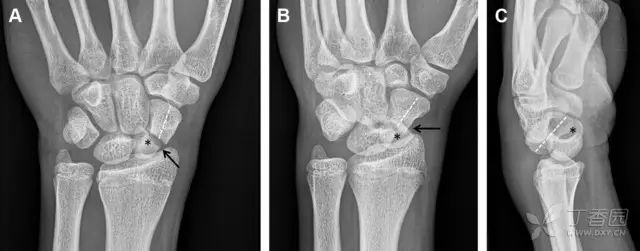

常规进行前后位、侧位、斜位 X 线检查,对于大多数桡骨远端骨折来说不容易漏诊;但是对于无移位的骨折,特别是桡骨茎突骨折,容易漏诊。桡骨茎突骨折是一斜行的骨折,常累及关节面,常发生于轴向应力或直接打击。

图 1 57 岁女性,摔倒后手掌撑地,桡骨茎突压痛。(A~C)前后位、斜位、侧位片示软组织肿胀(*)和发丝样骨折(白色箭头);(D~F)2 周后,前后位、斜位、侧位片示骨折线显明,由于新骨痂沉积而呈现透亮线与硬化线并存;(G~I)另一患者,桡骨茎突骨折在前后位及侧位片上显示不明显,而在斜位片显示更清楚

舟状骨骨折 60%~70% 发生于腰部,15% 发生于近极, 10% 发生于远极, 8% 发生于远端关节面。除了常规的前后位、侧位、斜位片外,还需要拍专门的舟状骨位片(腕关节尺偏,以舟状骨为中心的腕关节前后位片),特别是鼻烟壶有压痛时。

图 2 舟状骨骨折 (A、B)第 1 例患者,舟状骨远极关节内骨折(白色箭头),斜位片显示较清楚(B);(C、D)第 2 例患者,舟状骨腰部骨折(虚线箭头),斜位片显示较清楚(D);(E~H)第 3 例患者,舟状骨近极骨折,常规 X 线片均未看到骨折,而在舟状骨位片上才能见到骨折(虚线圆)

掌板是掌指关节和指间关节关节囊掌侧的纤维结构,防止关节过伸。掌板的远端部是增厚的纤维软骨,附着于指骨掌侧基底部,而其两侧与侧副韧带的纤维融合。掌板骨折多发生于过伸损伤,为撕脱性骨折。

图 3 掌板骨折(A~C)小指前后位、斜位、侧位片,由于骨折的部位及特点,在前后位片上通常难以发现骨折;放大后的斜位(D)、侧位(E)可见一骨碎片(白色箭头)

腕掌关节骨折脱位为高能量损伤,常伴有神经损伤。腕掌关节组成骨多,侧位片上重叠遮挡多,骨折不易发现,容易漏诊。在前后位片上,关节面不平滑、关节间隙不对称、关节皮质破坏、关节面重叠常提示腕掌关节骨折脱位。特别是第 4、5 腕掌关节脱位,在前后位片上不容易发现;该损伤不稳定,也称为「变异型拳击手损伤/骨折」。

图 4 第 4、5 腕掌关节骨折脱位。(A)正常腕掌关节,关节面平衡起伏、平行;前后位(B)、斜位(C)、侧位(D),第 5 掌骨近端附近软组织肿胀(白色箭头),冠状面关节面重叠,背侧撞击剪切应力致钩状骨骨折(*),在前后位及斜位片上可见双密度影。第 4 掌骨底部可见微小骨折碎片(D,虚线箭头),第 4、5 掌骨掌侧成角。(E~G)变异型拳击手损伤:第 4、5 掌骨背侧脱位而未见骨折(E,虚线方框),钩状骨有骨折小碎片(F,短虚线箭头),第 4 掌骨基底部关节内骨折(G,长虚线箭头)

钩状骨骨折可发生于体部和钩部,钩部骨折更多见,可合并有第 4、5 腕掌关节脱位。受伤机制由直接暴力或腕横韧带撕脱伤所致。骨折征象包括钩部无显示、骨皮质边缘模糊、硬化或双密度影等。常规的正侧位常无法明确诊断,需要加拍腕管位,可清晰显示其钩部。

图 5 打高尔夫球后腕部急性疼痛。常规腕关节 X 线片正常(X)。腕管位片(B)隐约可见钩部横行骨折(虚线箭头),CT 检查(C、D)进一步明确了诊断

三角骨骨折是除舟状骨骨折外腕关节常见的骨折之一。其背侧是背侧桡腕韧带的附着点,因此背侧骨折更常见。常规正侧位片基本可明确诊断。背侧骨折可在侧位片上看到一小骨块。

图 6 三角骨骨折。(A)前后位片骨折不明显,(B)仅在侧位片上见一小骨块(短箭头),伴有软组织肿胀(长箭头)。

月骨周围脱位和月骨周围骨折脱位常发生于摔倒后手掌撑地,由过伸、轴向暴力所致。所谓的「脆弱区」包括桡骨茎突、大多角骨、舟状骨、头状骨近端、钩状骨近端、三角骨的月骨缘、尺骨茎突。

图 7 经舟状骨骨折月骨周围脱位(腕关节前后位、斜位、侧位)。(A,B)前后位、斜位示月骨腰部骨折(黑箭头),第 1、2 腕弧中断,舟状骨近极(*)仍在原位,而远极(虚线)背侧脱位